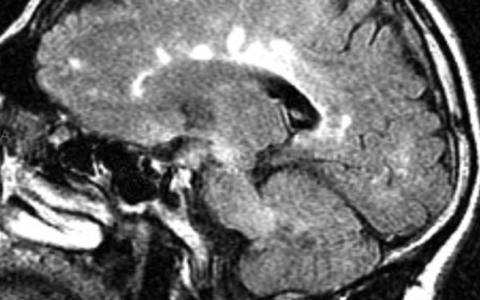

A 4-year-old girl presents to her pediatrician, who obtains the peripheral blood smear shown in the image. The loss of function of what body part will cause her to become symptomatic?

该血涂片显示丰富的淋巴母细胞,是急性淋巴细胞白血病 (ALL) 的典型特征。淋巴母细胞与正常成熟淋巴细胞的区别在于其细而均匀的染色、不规则的核边界和较少的细胞质。ALL 是一种起源于单个 B 或 T 淋巴细胞祖细胞的肿瘤。原始细胞在骨髓中增殖和蓄积,挤出其他血细胞系,导致造血抑制。最终,患者出现症状性贫血、血小板减少和中性粒细胞减少。